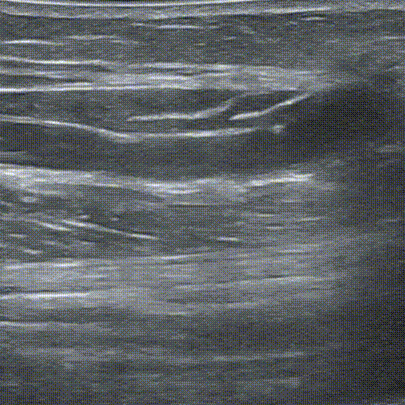

桡动脉近心端管径约4.2mm,桡动脉远心端闭塞,动脉近吻合口处内膜增生,至管腔狭窄,约1.8mm,为S1狭窄处。近吻合口头静脉内膜增生性狭窄S2,最小内径1.5mm,相邻内径约3.5mm,范围约3cm。